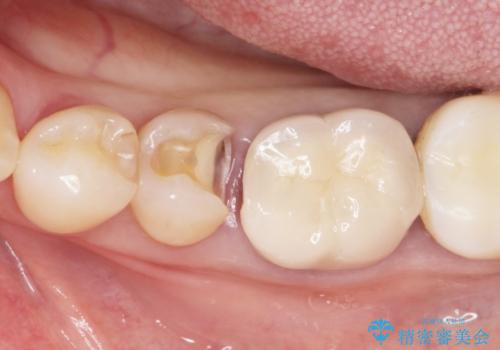

精査したところ、左下の奥歯(左下5)のプラスチックの詰め物と歯の境目が虫歯になり、黒くなっていました。

古い詰め物とう蝕を除去し、審美的で適合が良く二次う蝕になりにくいセラミックインレーによる修復を行いました。